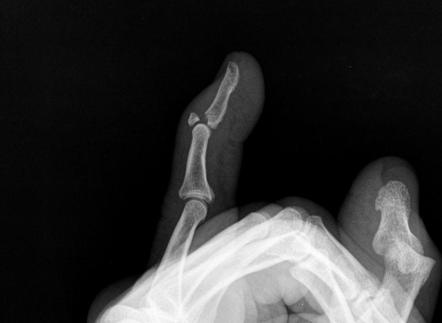

Que fractura se presenta en esta rx

Fractura del cuello del 5to metacariano (del mal boxeador)

Tratamiento de esta fractura

Reduccion cerrada: Maniobra de jazz (compresión en pinza con dedo pulgar, indice y dedo medio haciendo algo de traccion y manteniendo reducción palmar)

Molde de yeso tipo guante

Quirurgico: Placas pequeñas